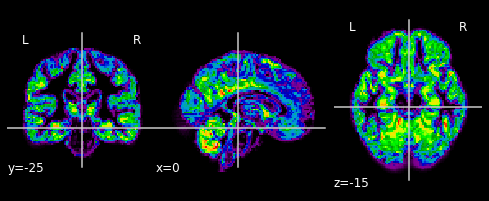

… and plot their gray matter densities.

for i in range(n_subjects):

plotting.plot_epi(gm_imgs[i])

plt.show()